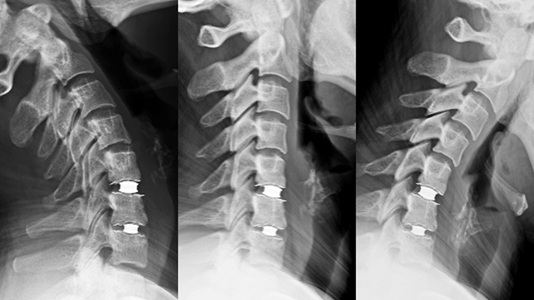

Newport Beach, California, July 31, 2025 / PRNewswire / – Artificial disk replacement (ADR): A procedure used to treat spinal stenosis, the degeneration of the disc and the disc herniation in the cervical spine – it can be performed safely and efficiently at multiple levels in the outpatient environment, according to the results of the newly released investigations. Written by the surgeon of the orthopedic column trained in the clinic, Steven J. Goldler, MD, a summary of these findings summarized six years of patient data during which surgeons of ADR performed surgeons in the locations of the disc centers in Newport Beach and Marina del Rey, California.

The analysis included 1,684 cervical artificial discs implemented in 1,043 patients, reviewing demographic data, ASA classifications, surgical times, patient results and costs. Of the 443 women, 559 men and 1 non -classified patient studied, there were zero immediate postoperative transfers, without blood transfusions and without re -entry within the immediate perioperative period. All patients were discharged at home successfully within 24 hours to begin their recovery.

Demonstrating ADR’s efficiency as an outpatient procedure regardless of the level, the decomposition of the case included 433 ADR of a single level with an average surgical time of 69.8 minutes; 579 ADR of two levels with an average surgical time of 93.4 minutes; and 31 ADR of three levels with an average surgical time of 131.8 minutes. These data reinforce the mission of the Trasmd Disco Surgery Center so that movement preservation procedures such as this are more accessible to patients while maintaining strict quality guidelines. Read the summary here.